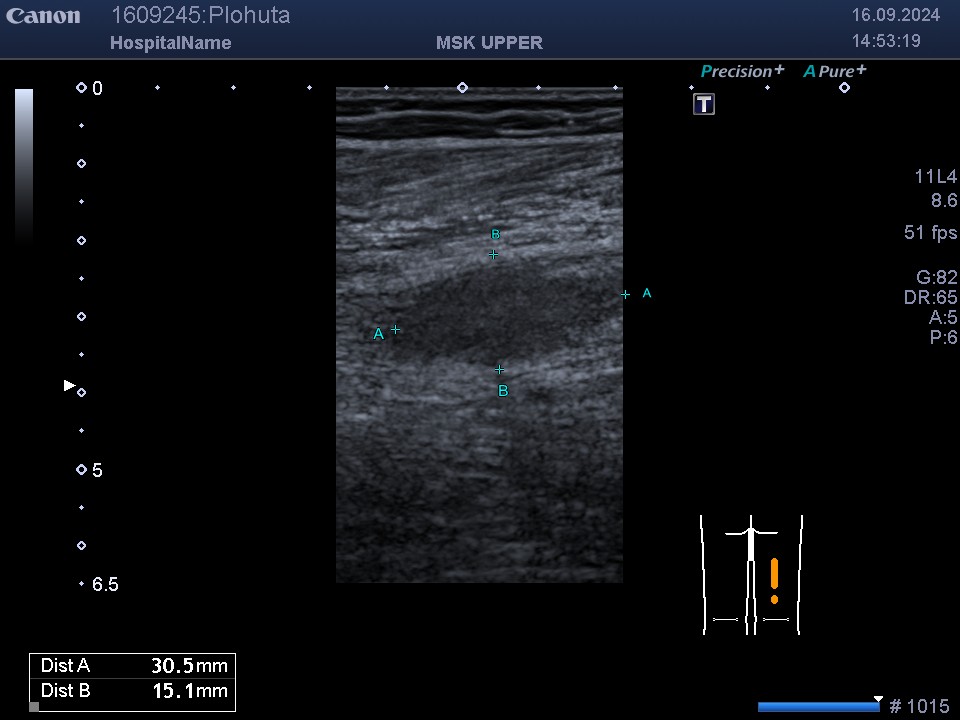

В нашому кабінеті УЗД Medicine Group проводять багато видів УЗД, але можливо не всі чули про УЗД нервів .Це дослідження досить не...

УЗД нервів та м’яких тканин. Якщо Ви думаєте, що дослідження нервів та м’яких тканин легко, то хочемо Вас розчарувати. Щоб...